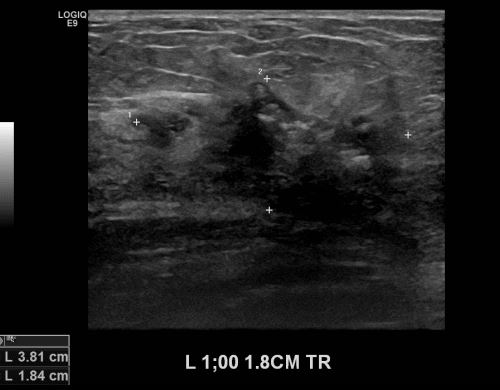

상기환자 건강건진상 이상 소견으로 내원하신 60대 여성분으로 본원 초음파상 좌측 유방

1시 방향에서 1.8cm 떨어진 거리의 의심스러운 멍울 조직검사 시행하여 좌측 침윤성

유관암 진단 되었습니다.